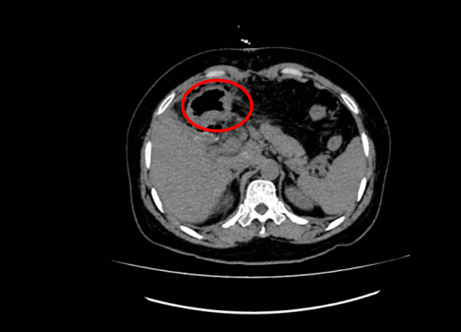

王女士入院后,检查结果令人忧心。她的肝脏占位病变,尤其是左肝肿瘤体积巨大,且与肝门及肝脏内大血管紧密相连,手术难度较大。面对挑战,潘耀振教授带领团队组织多学科专家会诊,认真研究了患者的病史,进行相关辅助检查,全面评估了患者病情,充分结合家属的顾虑因素,果断决定为王女士行肝癌切除+胆囊切除术的治疗方案。

近日,由潘耀振教授主刀,带领王兴副主任及团队实施了手术。腹腔探查见患者肿瘤位于左肝,呈突出性生长,巨大的包块令人触目惊心,与周围组织重度粘连,肿瘤压迫了胃、胰腺、结肠等重要脏器,但肿瘤医院的外科专家们凭借精湛的技术,术中精细操作、默契配合,成功完成了扩大左半肝及肿瘤的切除,取出的肿瘤尺寸达18x14cm,术中出血量极少,手术非常成功。

患者术前影像